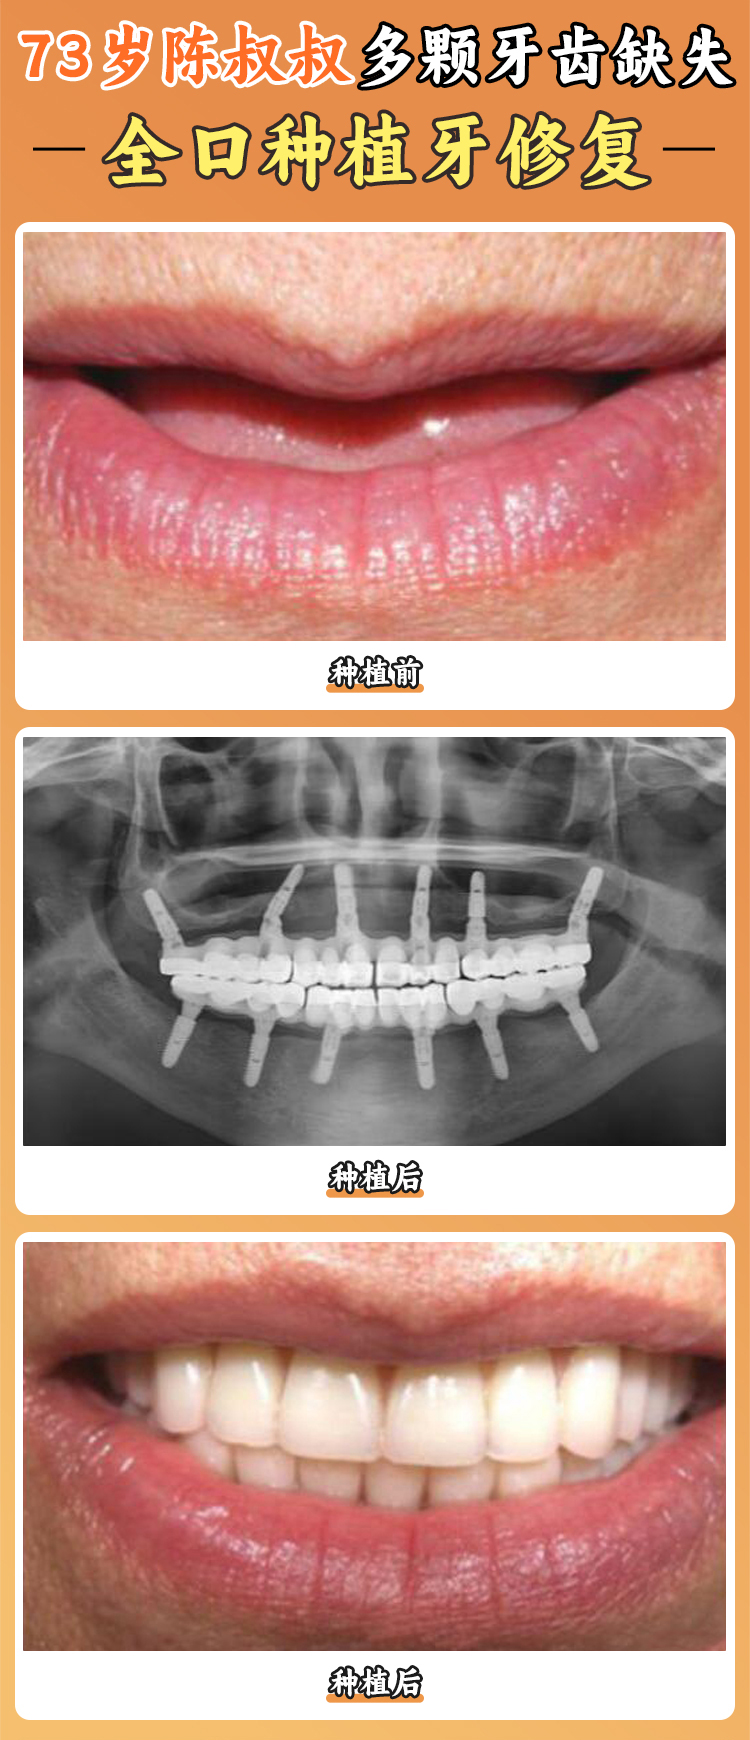

醫(yī)院擁有一支由經(jīng)驗充足的口腔種植醫(yī)師組成的醫(yī)療團隊。這些醫(yī)生就像是經(jīng)驗多的工匠,具備扎實的專科知識和豐富的臨床經(jīng)驗。他們能夠根據(jù)每個患者的不同情況,提供個性化的種植方案,就像為每個人量身定制一件衣服一樣。比如,有的患者牙槽骨條件不太好,醫(yī)生就會采用特殊的種植技術(shù)和方案,確保手術(shù)的可靠性和成效。有一位患者牙齒缺失多年,牙槽骨萎縮重度,其他醫(yī)院都表示治療難度大,但在寧波好牙引領(lǐng)口腔醫(yī)院,醫(yī)生憑借豐富的經(jīng)驗和不錯的技術(shù),成功為他種上了牙齒。